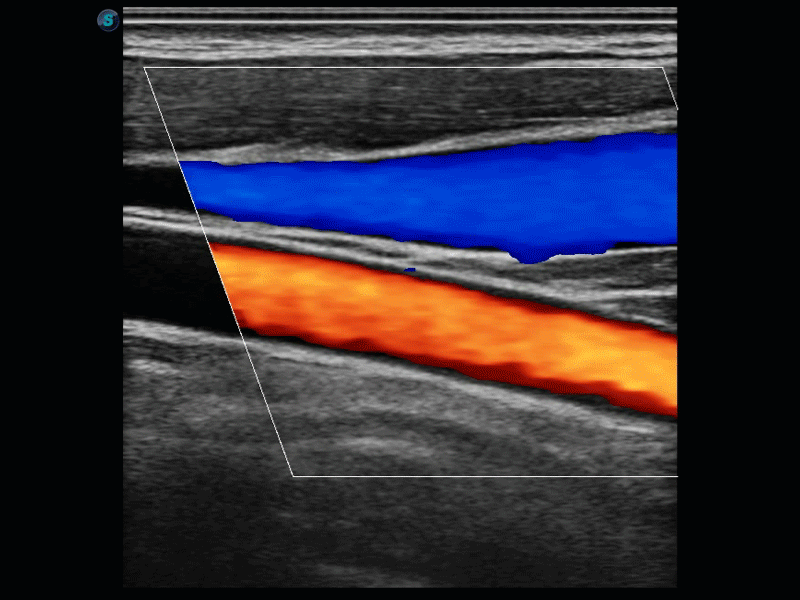

SR Flow高分辨率血流成像

高分辨率血流成像技术提高了对低速血流信号的检测能力。在提高空间分辨率的同时,也克服了血流外溢现象,为用户提供更加真实的血流动力学信息。

实时宽景成像技术

通过彩色血流和实时宽景相结合,可观察到完整的动静脉血流,方便医生检查。实时扫查过程中,如有任何操作失误也可以很容易地进行回扫擦除,而不会中断扫查。

临床图像